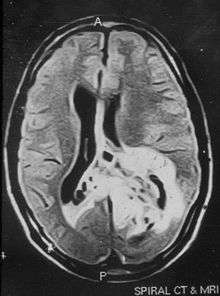

Due to the large range of causes that lead to micropsia, diagnosis varies among cases. Computed tomography (CT) and magnetic resonance imaging (MRI) may find lesions and hypodense areas in the temporal and occipital lobes.[8] MRI and CT techniques are able to rule out lesions as the cause for micropsia, but are not sufficient to diagnose the most common causes.